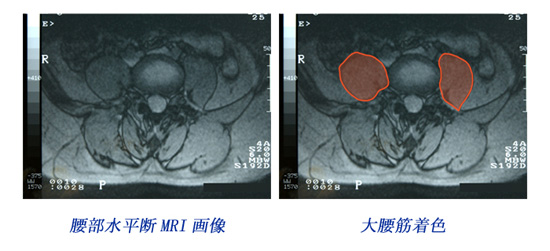

腰部MRI(大腰筋)画像

ヒントとして腰部MRI画像を掲載します。なおこのMRI画像は上部シルエット患者のものではありません。画像の左右に注意し、大腰筋に着目し熟慮してください。